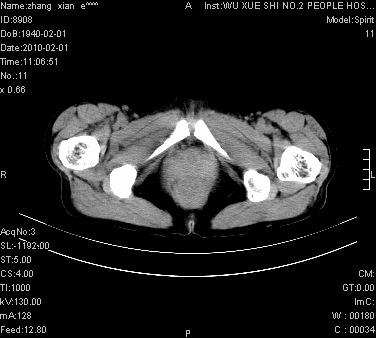

标题: CT24434:70岁 女 腹胀,腹水原因待查 [打印本页]

标题: CT24434:70岁 女 腹胀,腹水原因待查

大量腹水,脾脏囊性占位,子宫颈占位,右侧腹股沟淋巴结肿大,建议+c,先查妇科。

腹盆腔大量积液,子宫增大,子宫颈增大外形不规则,内见低密度影,膀胱后壁显示不清,右腹股沟肿大淋巴结,脾脏囊性占位,子宫颈占位,子宫颈癌?建议增强。

腹盆腔大量积液,子宫增大,子宫颈增大外形不规则,内见低密度影,膀胱后壁显示不清,右腹股沟肿大淋巴结,脾脏囊性占位,子宫颈占位,子宫颈癌?建议增强。支持!